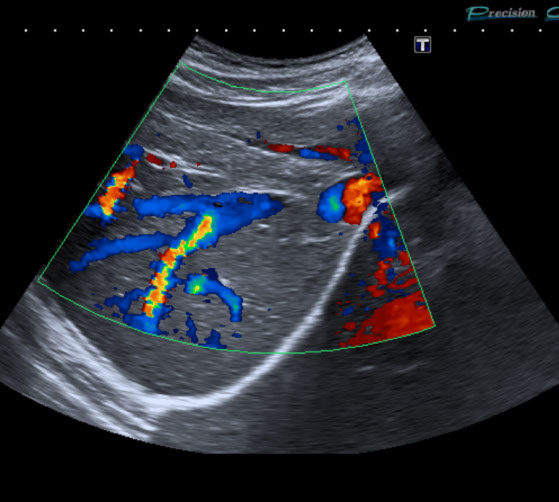

Gefäßultraschall /

Farbdopplersonographie

Die Farbdopplersonographie ist eine zuverlässige Methode zur Beurteilung von Arterien und Venen. Die Farbdopplersonographie kann einerseits Veränderungen der Gefäßwände (z.B. arteriosklerotische Plaques) und dadurch resultierende Engstellen (Stenosen) nachweisen, andererseits durch Blutflussgeschwindigkeitsmessungen den Schweregrad der Stenosen beurteilen. Risikofaktoren für Arteriosklerose und damit für Schlaganfall und Herzinfarkt sind z.B. erhöhte Blutfettwerte, hoher Blutdruck (Hypertonus), Nikotinkonsum.

• Die großen Bauchgefäße (speziell Bauchschlagader) zur Erfassung von Gefäßaussackungen (Aneurysmen) oder Engstellen (Stenosen) sowie bei Verschlüssen, Thrombosen der Pfortader und anderer Bauch- und Beckengefäße.